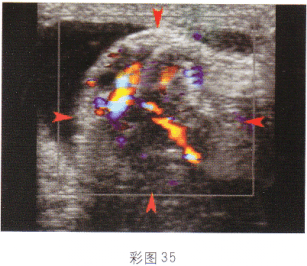

根据超声图像所示(彩图35),最可能的诊断是

• A.附睾炎

• B.睾丸扭转

• C.卵巢囊肿蒂扭转

• D.子宫腺肌病

• E.附睾精液囊肿